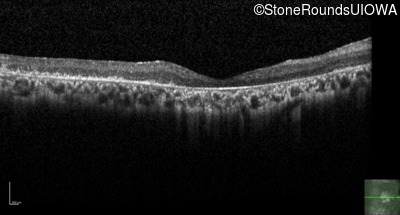

The clinical features supporting the diagnosis of Bardet Biedl syndrome in this patient include: bone-spicule-like pigmentation, narrowed arterioles and macular atrophy on ophthalmoscopy; photoreceptor loss on OCT; ulnar polydactyly, obesity, abnormal cognition, hypertension; and, normally sighted parents.